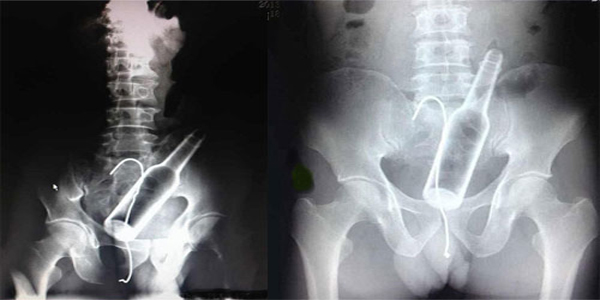

बीजिंग: चीन में एक हैरान करने वाला मामला सामने आया है, जिसमें एक व्यक्ति के पेट में दर्द का कारण एक बोतल निकला। आखिर ये हुआ कैसे? पूरा मामला तब सामने आया, जब इस शख्स के पेट में असहनीय दर्द शुरू हुआ। उसे यह समझ न आए कि आखिर उसने ऐसा क्या खा लिया है, जो इस तरह का दर्द शुरू हो गया है।

हफपोस्ट की खबर के अनुसार, वह जल्द से चीन के इस अस्‍पताल में पहुंचा और असहनीय पेट दर्द के बारे में बताया। सब की आंखे तब फटी की फटी रह गई, जब डॉक्‍टरों ने उसका एक्‍स-रे कि‍या और पेट में बोतल की बात बताई। इस शख्‍स की गुदा में एक बोतल फंसी हुई थी, जो इस दर्द का कारण था।

इस पर उस शख्स ने बताया कि एक बार वह बोतल पर बैठ गया था, जि‍ससे वह गुदा के रास्‍ते अंदर चली गई और बहुत कोशिश करने पर भी वह निकाल न पाया। हालांकि अब डॉक्‍टरों ने उसका ऑपरेशन करके बोतल को नि‍काल दि‍या है। डॉक्‍टर ने बताया कि वैसे तो ऐसे मामलों में जब कोई बाहरी चीज शरीर के अंदर चली जाती है तो उसे तार की मदद से बाहर नि‍काल दि‍या जाता है, लेकि‍न इस मामले में ऐसा नहीं हो सका, इसलि‍ए उन्‍हें सर्जरी करके ही इस बोतल को बाहर नि‍कालना पड़ा।